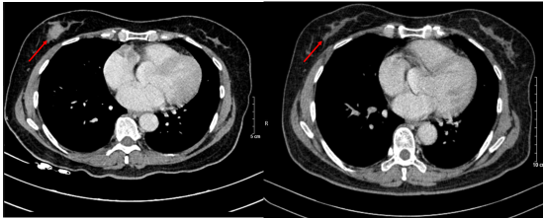

Chụp cắt lớp vi tính lồng ngực: Không phát hiện hình ảnh bất thường ở nhu mô vú phải.

Hình 6. Hình ảnh CT u vú trước điều trị (bên trái) và sau điều trị (bên phải): Trước điều trị: 1/4 dưới ngoài vú phải có nốt đường kính 20mm, bờ ranh giới không rõ, ngấm thuốc sau tiêm. Sau điều trị: Không phát hiện hình ảnh bất thường ở nhu mô vú phải.